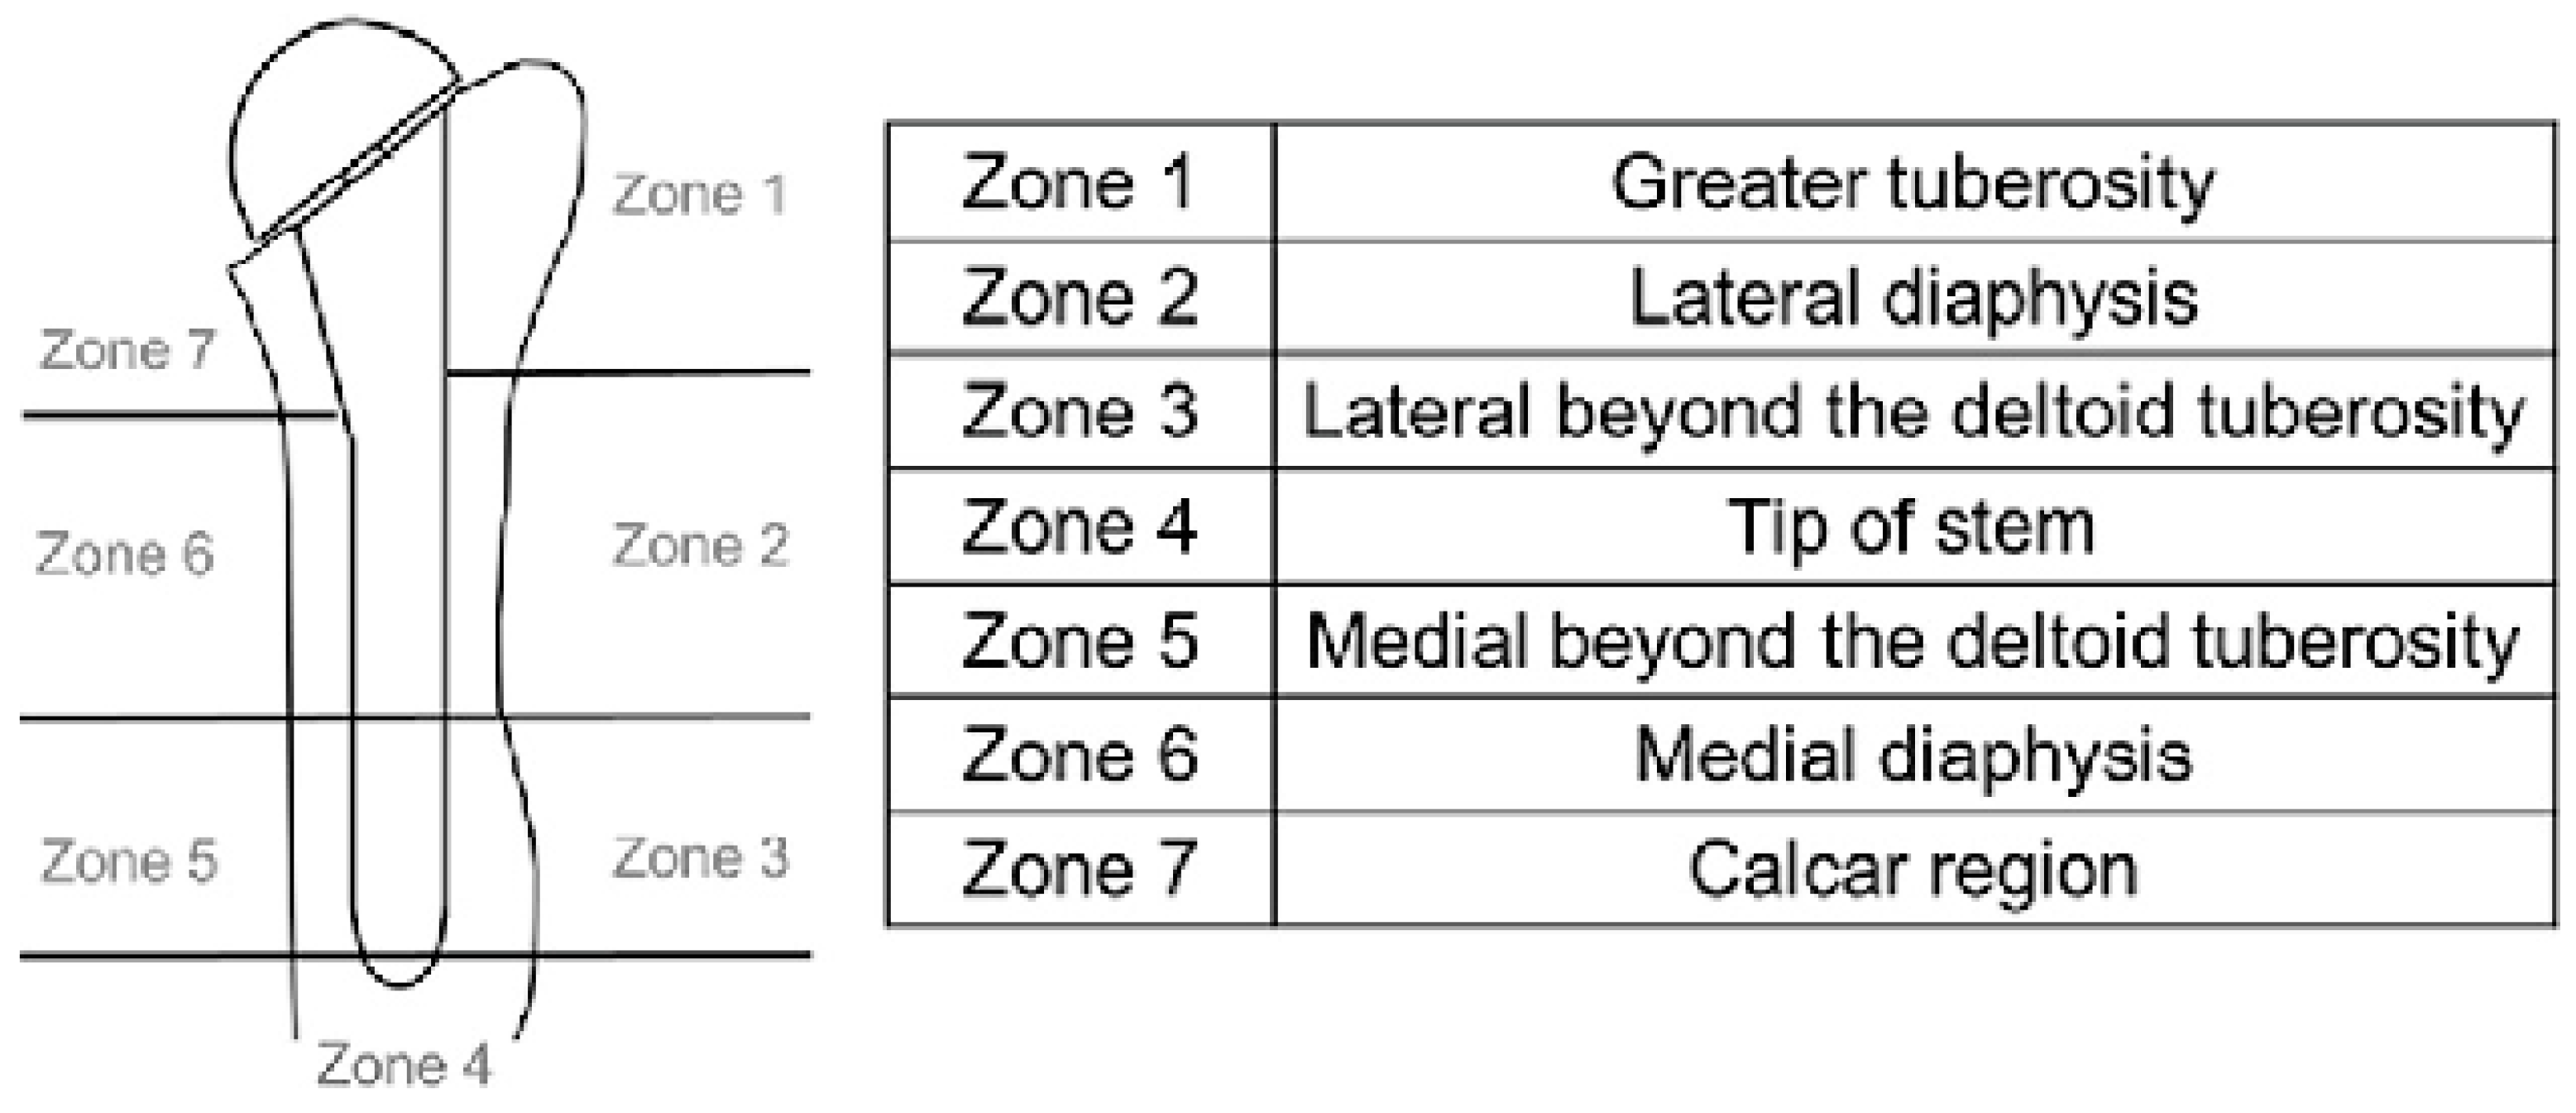

3.2. Radiological Outcomes

4.2. Radiological Outcomes

| Sum Inoue score | 2.57 ± 2.99 | 2.43 ± 2.79 | 0.33 |

| Zone 1, mean ± SD | 0.91 ± 1.26 | 0.81 ± 1.35 | 0.38 |

| Zone 2 | 0.64 ± 0.92 | 0.61 ± 1.03 | 0.17 |

| Zone 3 | 0.06 ± 0.23 | 0.08 ± 0.40 | 0.11 |

| Zone 4 | 0 | 0 | - |

| Zone 5 | 0 | 0 | - |

| Zone 6 | 0.15 ± 0.36 | 0.17 ± 0.53 | 0.24 |

| Zone 7 | 0.81 ± 0.81 | 0.74 ± 1.02 | 0.41 |

| Sirveaux | 0.264 ± 0.52 | 0.278 ± 0.51 | 0.85 |